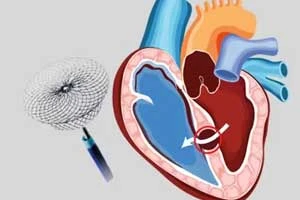

PTCA / Angioplasty with Stent

Minimally invasive procedure to open blocked arteries

PTCA / Angioplasty with Stent

Minimally invasive procedure to open blocked arteries

TAVR / TAVI

Transcatheter aortic valve replacement procedure

TMVR

Transcatheter mitral valve repair/replacement